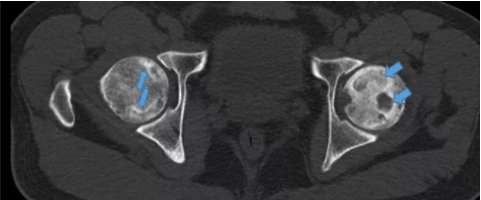

病例1-3 示双股骨头内线状高密度影,右侧股骨头内坏死区密度增高;左侧股骨头密度不均,可见多个囊状透亮区;左侧股骨头关节面塌陷呈台阶状。诊断为双侧股骨头坏死,左侧为Ⅲ期,右侧为Ⅱ期。

病例1-4 示双股骨头内线状高密度影,双侧股骨头内坏死区密度增高;双侧股骨头密度不均,可见囊状透亮区;双侧股骨头关节面塌陷呈台阶状。诊断为双侧股骨头坏死,左侧为III期,右侧为III期。